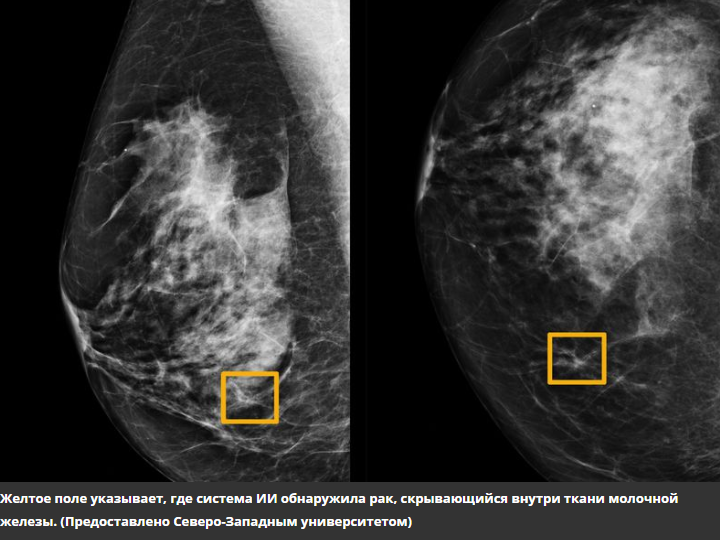

Система анализирует маммограммы, выявляет и идентифицирует злокачественные и доброкачественные новообразования, кальцинаты, лимфатические узлы, фиброзно-кистозную мастопатию, определяет плотность ткани молочной железы в соответствии с ACR и назначает категорию исследований bi-RADS. Пакет из четырех проекций (RCC, RMLO, LCC, LMLO) обрабатывается менее чем за 60 секунд.

Проводя скрининг, система выявляет наличие новообразований и ранжирует осмотры в соответствии с приоритетами: прежде всего, врач изучает снимки пациентов с подозрением на отклонения от нормы.

В ходе диагностики система определяет наличие новообразований и обозначает области, представляющие интерес на изображении, чтобы врач не упускал из виду патологию. В сервисе реализованы основные инструменты для работы с изображениями: изменение яркости, контрастность, инверсия и возможность увеличение изображения.

При пакетной обработке система ранжирует список исследований в соответствии с приоритетами, выявляет наличие доброкачественных или злокачественных изменений и указывает их местонахождение. Сервис оптимизирует процесс подготовки медицинского заключения — автоматически генерирует описание изображения.